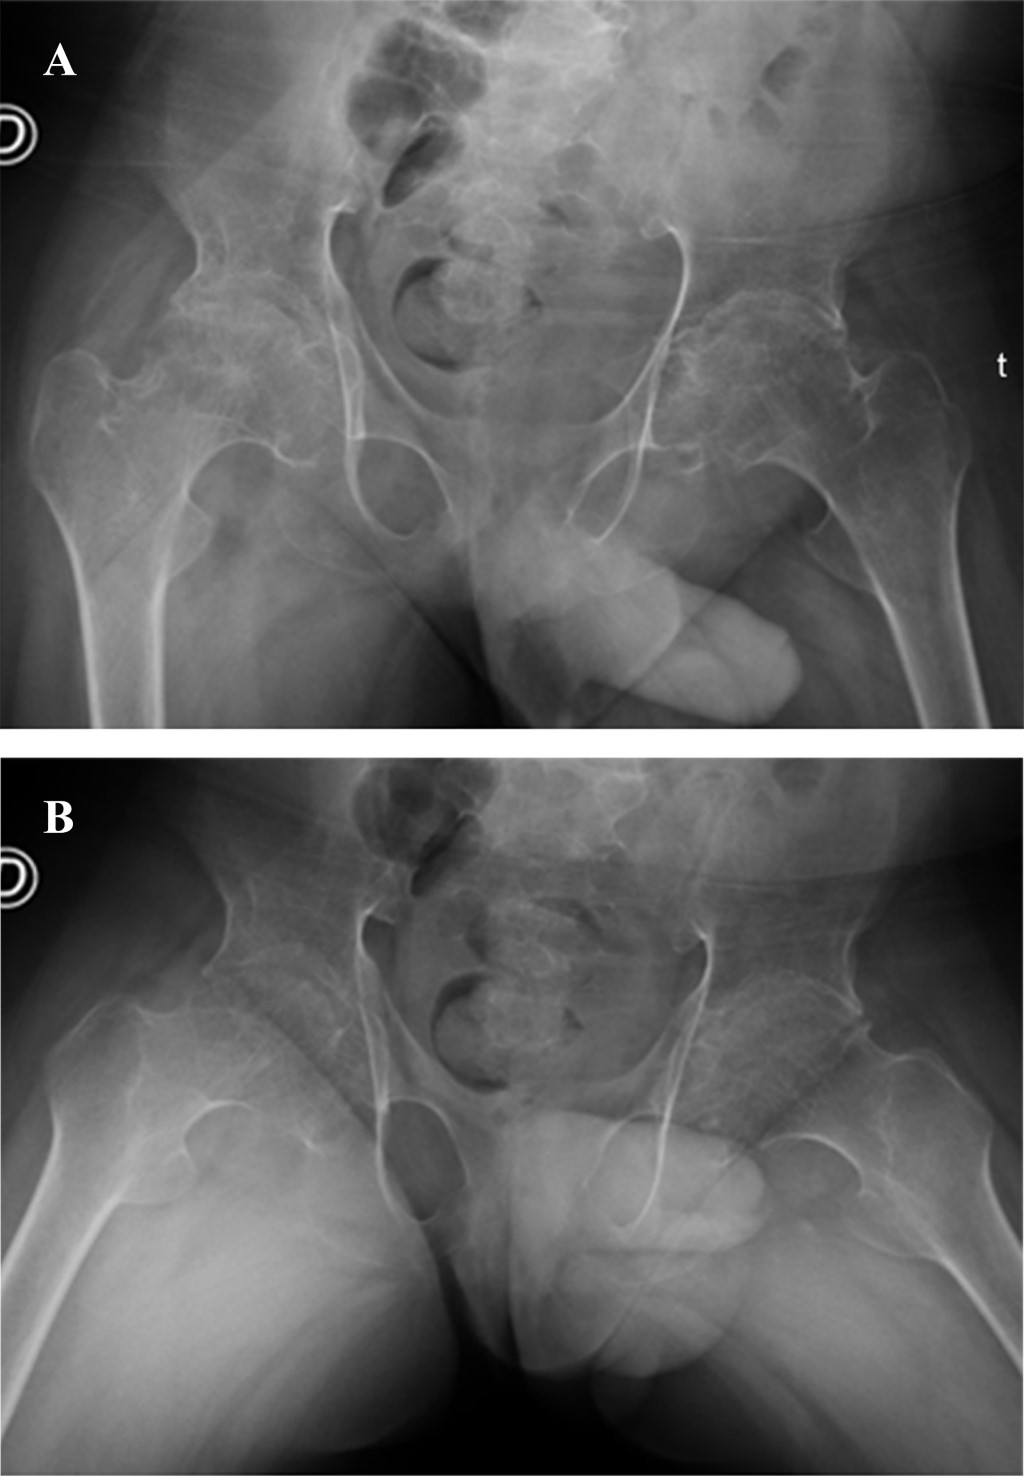

Progressive pseudorheumatoid dysplasia (PPD) is an autosomal recessive hereditary disease of very low prevalence. It is characterized by the affection of multiple joints, generating arthrosis and progressive deformities from a very young age, which significantly affect the quality of life of patients. Its diagnosis is only confirmed by genetic testing, and no specific pharmacological treatment is still available. In the case of hip involvement, one treatment option is arthroplasty. In this case report, we present a 15-year-old boy with bilateral coxarthrosis secondary to PPD who underwent bilateral total hip arthroplasty in two stages. We highlight the characteristics of this rare entity, the intraoperative findings, the functional outcomes, and the impact on quality of life.

Figure 1